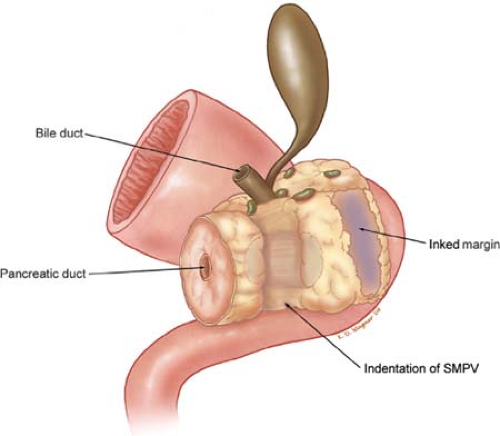

Фотографии медицинских исследований инсулиномы и синдрома Триады Уиппла